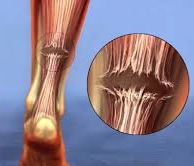

아킬레스건 이란?

비복근과 가자미근

2가지 근육이 연결되는

공통 힘줄입니다.

또 운동 중에

[힘줄 파열]**이 발생하는 경우가

있는데요.

초음파 검사에서

확인된 파열 범위에 따라

반드시 수술이 필요한 경우도

있습니다.

또한 아킬레스 힘줄은

직진하기 때문에

힘줄의 마찰을 줄여주는

건초가 없이

건막만 있는데요.

오래 서있거나

갑작스러운 운동으로

힘줄 주변에 염증이 생기거나

인근에 위치한

점액낭에 염증이 생기는 경우가

이를

[힘줄주위염, 점액낭염]

이라고 합니다.

이런 상태에서 충분히 쉬지 못하고

반복적으로 이어지면

힘줄에 염증물질이 축척되면서

힘줄 자체가 두꺼워지게 됩니다.

퇴행성 변화가 오게 되는 것이죠.